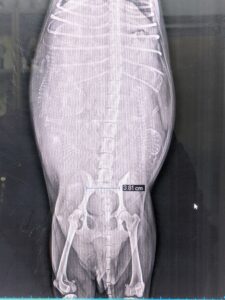

夕方、レントゲン検査撮影 2月1日

頭が5つ!!

降りてきてるようです。

みんな逆子です✧◝(⁰▿⁰)◜✧

産道も通れそうです。